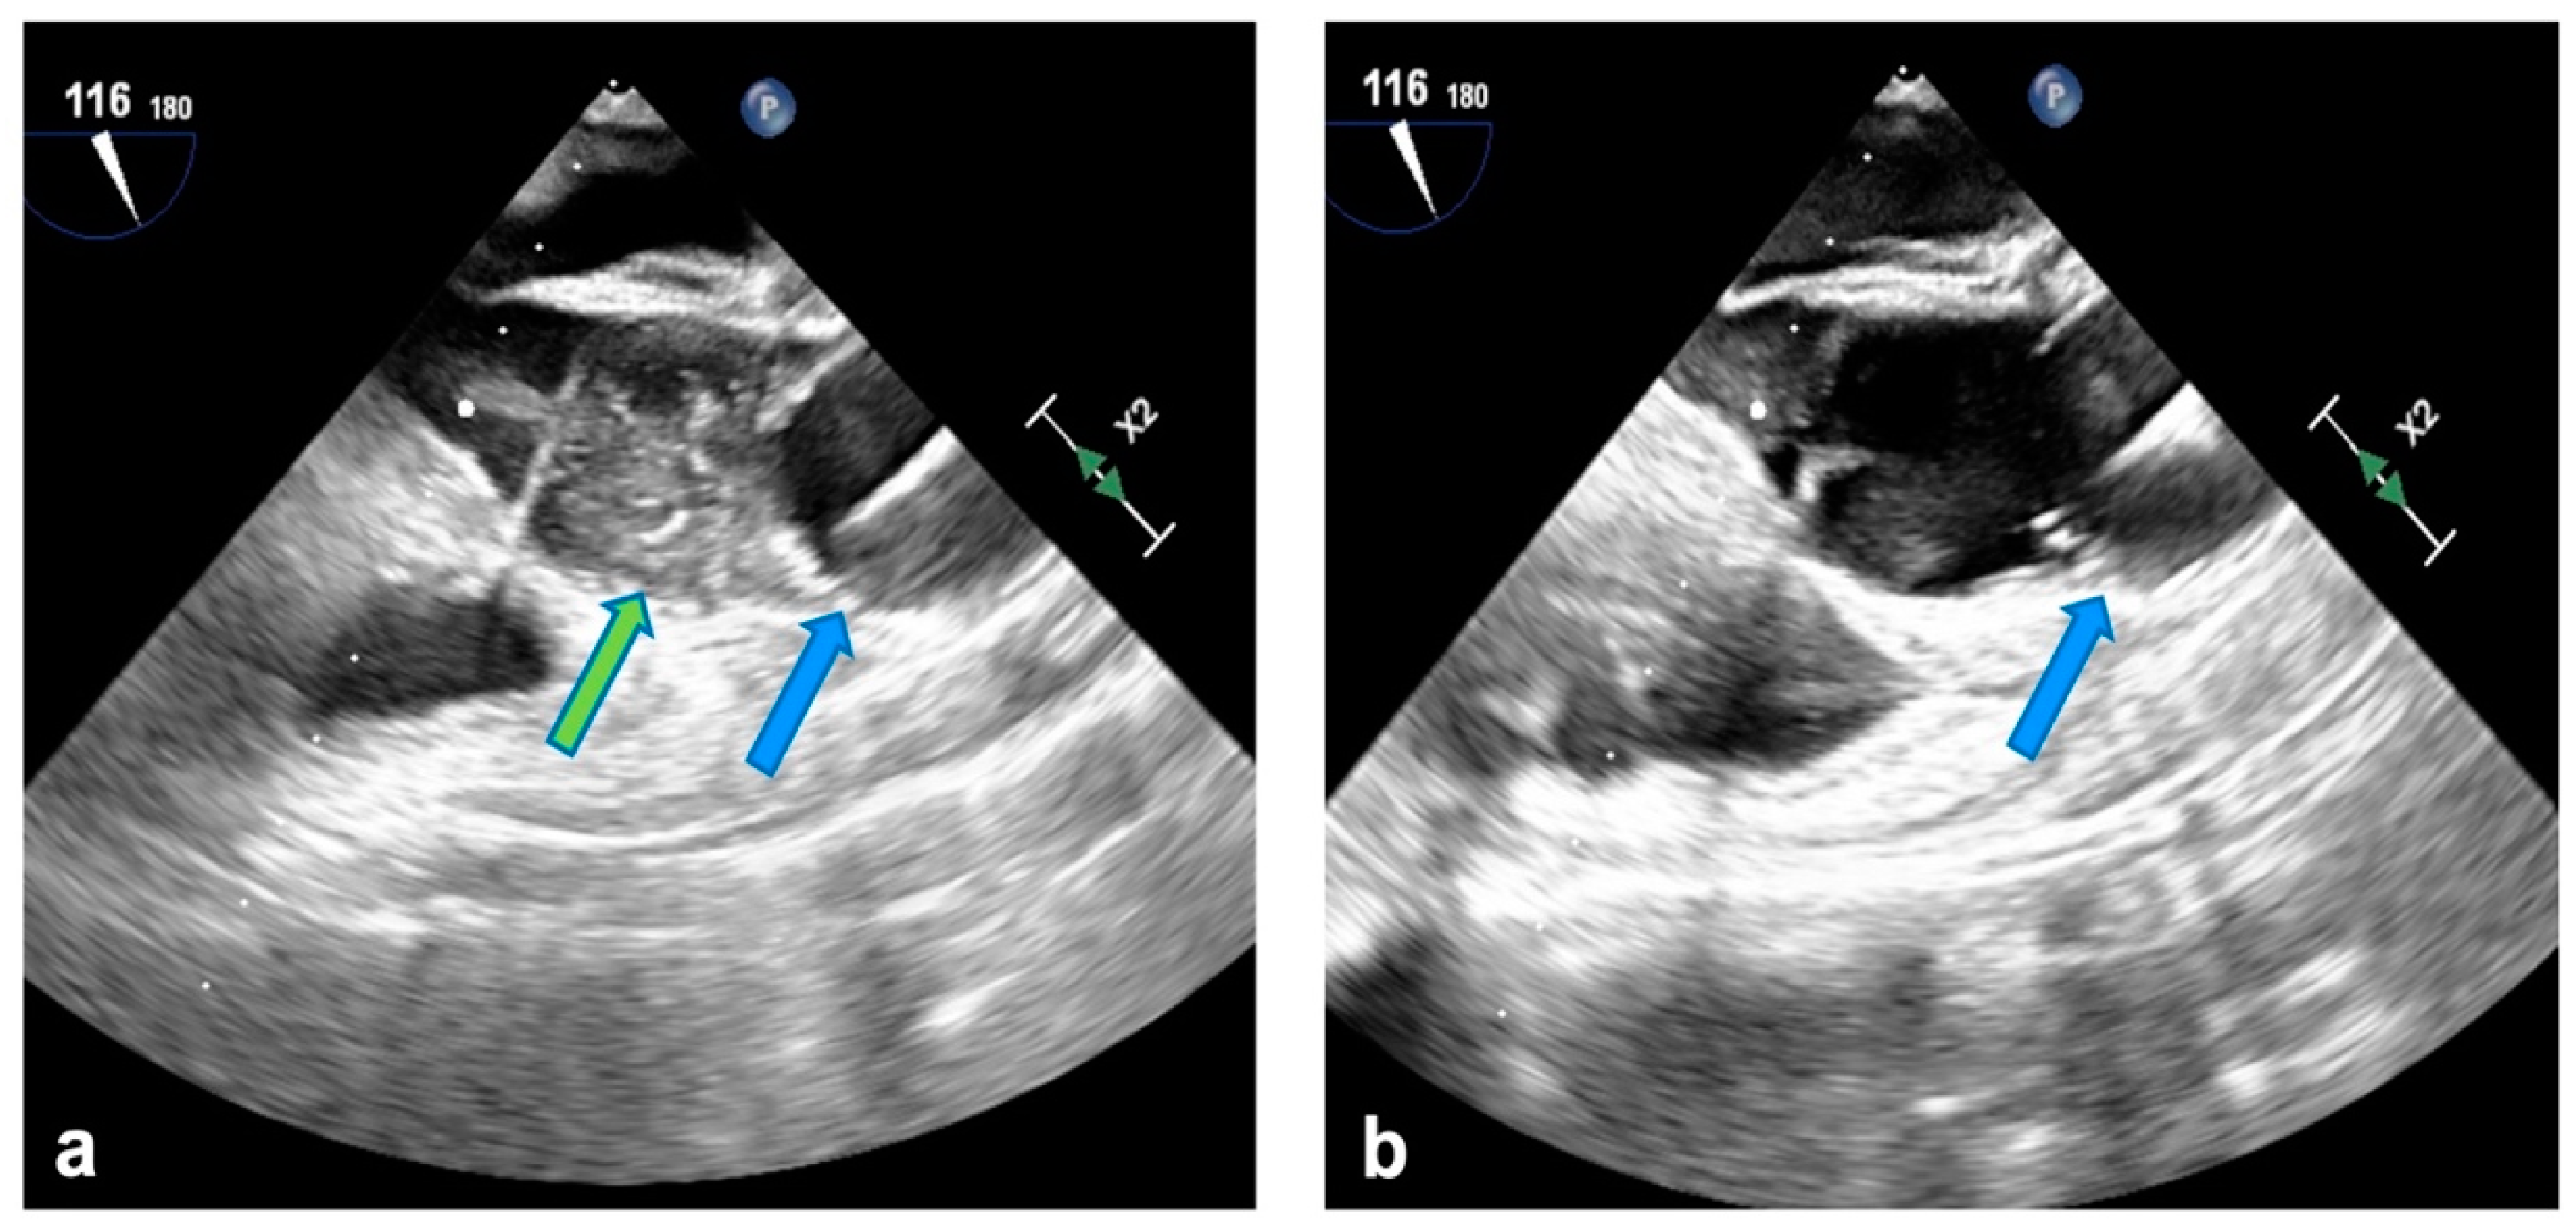

Clamping and cardioplegia delivery are obtained through the balloon catheter (Intraclude®, Edwards Lifesciences, Irvine, CA, USA) inserted through the sidearm of the arterial cannula. Antegrade myocardial protection is always provided with crystalloid St. Thomas hospital solution 1 (PlegisolTM, Hospira Inc., Lake Forest, IL, USA) or Bretschneider solution (Custodiol® HTK, Raleigh, NC, USA). Adenosine is infused directly in the aortic root to enhance immediate asystole, therefore enabling accurate and steady positioning of the balloon in the ascending aorta (Figure 1a). When feasible, removal of the crystalloid solution through a minimal right atrial incision is preferred to hemofiltration during CPB in patients receiving Bretschneider cardioplegia. Superior and inferior vena cava snaring are obtained by placing tourniquets around the vessels or with endovascular balloons. Continuous monitoring with transesophageal echocardiography is mandatory for proper positioning of the venous cannulae and to assess aortic occlusion and cardioplegia delivery and mitigate the hazards of endo-balloon migration towards the aortic arch or valve (Figure 1b). Furthermore, right radial arterial pressure is continuously monitored to promptly detect distal dislodgement because transesophageal echocardiographic views may prove inadequate in these conditions, delaying diagnosis.

Figure 1.

(a) Endo-aortic balloon in ascending aorta (blue arrow); cardioplegia delivery (green arrow). (b) Correct positioning of the endo-balloon in ascending aorta at the end of cardioplegia administration.